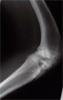

Xrays : 2nd stage tibia lengthening

Post

Op2

Distraction of corticotomy

Healing of regenerate